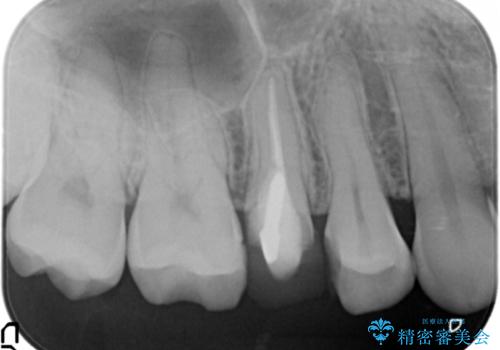

患者様の天然歯はグラデーションがあり切縁(歯冠の先端)はやや透けていて透明感があるのに対し、前歯(右上1)の差し歯はやや黄色く不透明で単調な色味でした。

患者様のご希望により、右上1はジルコニアクラウン(スペシャル)、右上5はジルコニアクラウン(スタンダード)へやりかえることにしました。

再根管治療に関しては、患者様がご希望されず症状もないため行っておりません。

ご予算の都合とご希望により、右上5の土台はやりかえずに元の土台のまま治療を進めました。